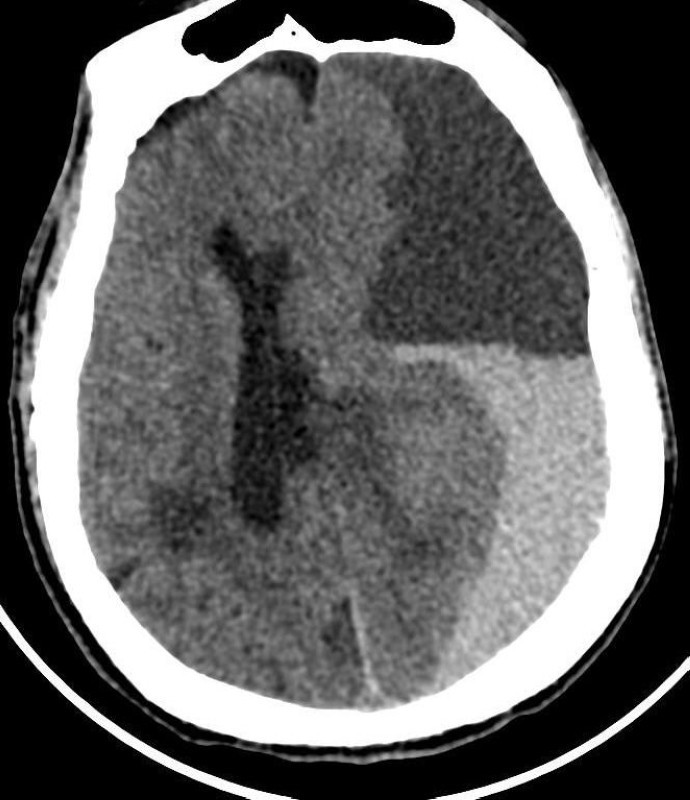

وبين رئيس الفريق الطبي استشاري جراحة المخ والأعصاب الدكتور زهير هوساوي أن المريضة حضرت إلى قسم الطوارئ وهي بغيبوبة كاملة وصعوبة في التنفس، وبشكل عاجل تم عمل الفحوصات الطبية اللازمة والأشعة وتبين وجود نزيف دماغي ضخم ضاغط على الدماغ، على إثره تقرر ضرورة نقل المريضة الى غرفة العمليات والتدخل الجراحي، مشيراً إلى أنه تم خلال العملية فتح الجمجمة وإيقاف النزيف، وتكللت العملية بالنجاح، وبعد ذلك نقلت المريضة للعناية المركزة ثم إلى قسم جراحة المخ والأعصاب، وتم بعد ذلك خروج المريضة من المستشفى وهي بصحة جيدة.